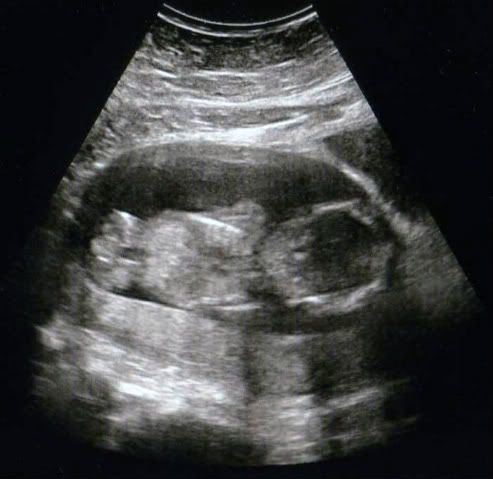

For all that asked.....results of our second growth scan..baby that active the doc couldnt measure things right. In the end they managed to grab a last quick photo shame baby turned just beforehand to show its backside to us!

we also had some possible bad news as well...feeling a little upset to talk at the minute and trying to make sure my OH's ok so if I do dissapear for a few days i'll be fine

the doc did say though "nice bum cheeks"